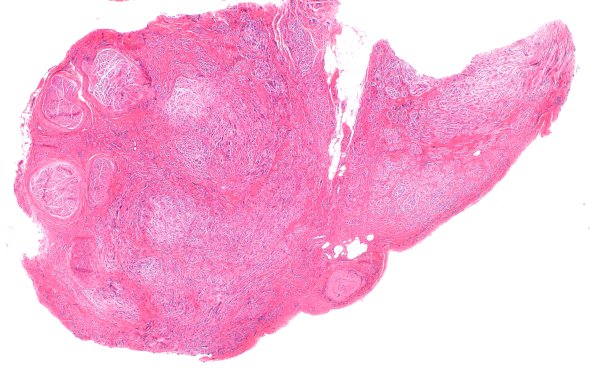

18A0 Neuroma (Case 18) H&E 2X